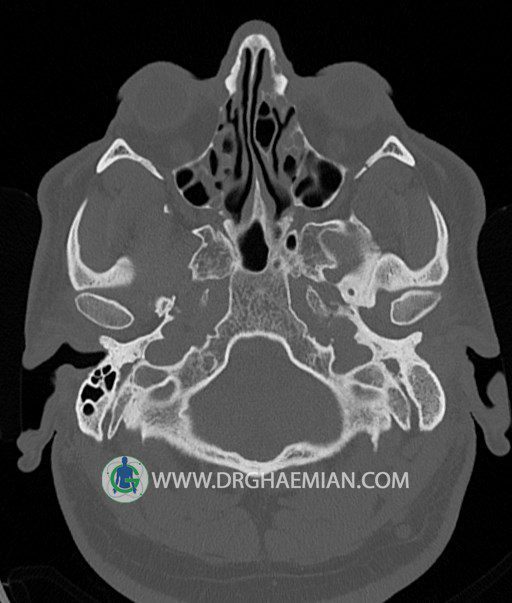

سی تی اسکن گوش داخلی به رادیولوژیست اجازه می دهد تا سطوح مختلف، یا اسلایس هایی از استخوان های که از جمجه به گوش می روند را از طریق امواج ایکس چرخشی مشاهده کند. در این کیس اودیت مدیا، ماستوئیدیت مزمن، اوتیت خارجی، انحراف سپتوم بینی، کونکا بولوزا و افزایش ضخامت سینوس ها مشاهده می شود.

در HRCT از استخوان تمپورال با مقاطع آگزيال ، ساژيتال و کرونال ظريف ( 0.6 mm ) :

– انحراف سپتوم مياني بيني به راست

– کونکا بولوزا در کونکاي مياني چپ و

– افزايش ضخامت مخاطي در سينوس هاي اتموئيد و ماگزيلاري

اپاسيته